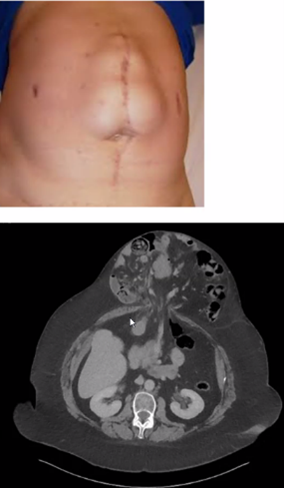

Vad ses på bilden? Hur sätter vi diagnos? Åtgärd?

A

Navelbråck/Epigastricabråck (övre del av bukvägg)

• Sitter ovanför naveln mellan xiphoideus och navel

• Diagnos: klinisk us, ev DT herniografi

• Åtgärd

o operativt: suturplastik (små defekter, <3 cm) nätplastik (sublay (nätet ligger framför peritoneum men under muskler och någon fascia), öppet/lap)

o konservativt (ej symtomgivande, BMI>30)

• Efter ex en lagning akut, då kan det vidga upp sig. Kan vara riktigt stort. Mkt kan ligga utanför.

• Utredning klinisk undersökning, DT herniografi

• Får bråckinnehållet plats i buken?

o Om nej – loss of Domain

o Konservativt: viktnedgång, sluta röka, gördel

o Operativt: Öppet (nätplastik sublay) eller Lap (nätplastik)